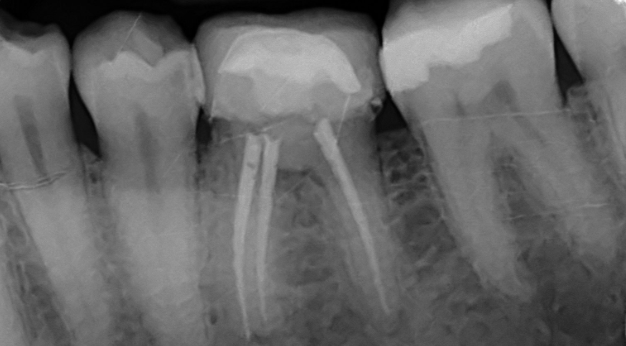

Endodoncia

• Tratamientos de conductos

• Salvamos dientes comprometidos

• Técnicas con microscopio